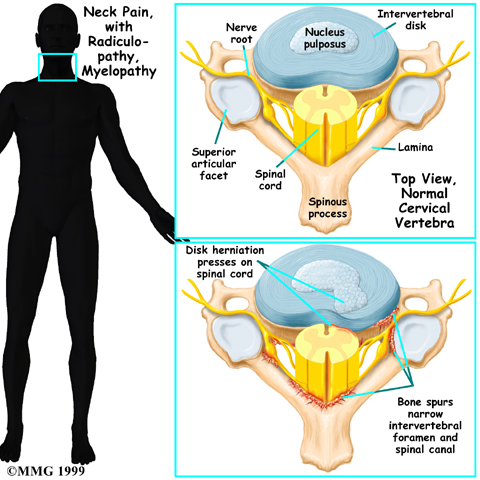

The nucleus may push through the weakened and torn annulus and into the spinal canal. This is called a herniated or ruptured disc. The disc material that squeezes out can press against the spinal nerves. The disc also emits enzymes and chemicals that produce inflammation. The combination of pressure on the nerves and inflammation caused by the chemicals released from the disc cause pain.

As the degeneration continues, bone spurs develop around the facet joints and around the disc. No one knows exactly why these bone spurs develop. Most doctors think that bone spurs are the body's attempt to stop the extra motion between the spinal segment. These bone spurs can cause problems by pressing on the nerves of the spine where they pass through the neural foramina. This pressure around the irritated nerve roots can cause pain, numbness, and weakness in the neck, arms, and hands.

Pressure or irritation in the nerves of the cervical spine can affect the nerves' electrical signals. The pressure or irritation can be felt as numbness on the skin, weakness in the muscles, or pain along the path of the nerve. Most people think of these symptoms as indications of a pinched nerve. Health care providers call this condition cervical radiculopathy.

Several conditions can cause radiculopathy. The most common are degeneration, disc herniation, and spinal instability.

- Degeneration: As the spine ages, several changes occur in the bones and soft tissues. The disc loses its water content and begins to collapse, causing the space between the vertebrae to narrow. The added pressure may irritate and inflame the facet joints, causing them to become enlarged. When this happens, the enlarged joints can press against the nerves going to the arm as they squeeze through the neural foramina. Degeneration can also cause bone spurs to develop. Bone spurs may put pressure on nerves and produce symptoms of cervical radiculopathy.

- Herniated Disc: Heavy, repetitive bending, twisting, and lifting can place extra pressure on the shock-absorbing nucleus of the disc. If great enough, this increased pressure can injure the annulus (the tough, outer ring of the disc). If the annulus ruptures or tears, the material in the nucleus can squeeze out of the disc. This is called a herniation. Although daily activities may cause the nucleus to press against the annulus, the body is normally able to withstand these pressures. However, as the annulus ages, it tends to crack and tear. It is repaired with scar tissue. Over time, the annulus becomes weakened, and the disc can more easily herniate through the damaged annulus.

If the herniated disc material presses against a nerve root it can cause pain, numbness, and weakness in the area the nerve supplies. This condition is called cervical radiculopathy (mentioned earlier). And any time the herniated nucleus contacts tissues outside the damaged annulus, it releases chemicals that cause inflammation and pain. If the nucleus herniates completely through the annulus, it may squeeze against the spinal cord. This causes a condition that is even more serious because it affects all the nerves of the spinal cord. This condition is called cervical myelopathy.

Cervical Myelopathy

Stenosis means closed in. Spinal stenosis refers to a condition in which the spinal cord is closed in, or compressed, inside the tube of the spinal canal. Spinal stenosis may be caused by degenerative changes, such as bone spurs pushing against the spinal cord within the spinal canal.

However, stenosis can also develop when a person of any age has a disc herniation that pushes against the spinal canal. When the spinal cord is squeezed in the neck, doctors call the condition cervical myelopathy. This is an alarming condition that demands medical attention. Cervical myelopathy can cause problems with the bowels and bladder, change the way you walk, and affect your ability to use your fingers and hand.